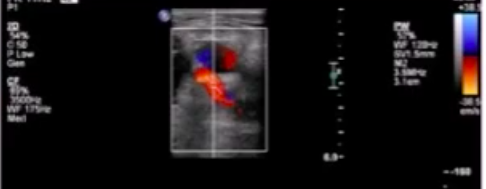

Low-resistance doppler signal in EIA 3 wks after LHC.

*EIA = external iliac artery

think of AV fistula

low-resistance doppler signal (LRDS) in the proximal iliofemoral arterial system after LHC→ think of AVF

shown below: LRDS in CFA